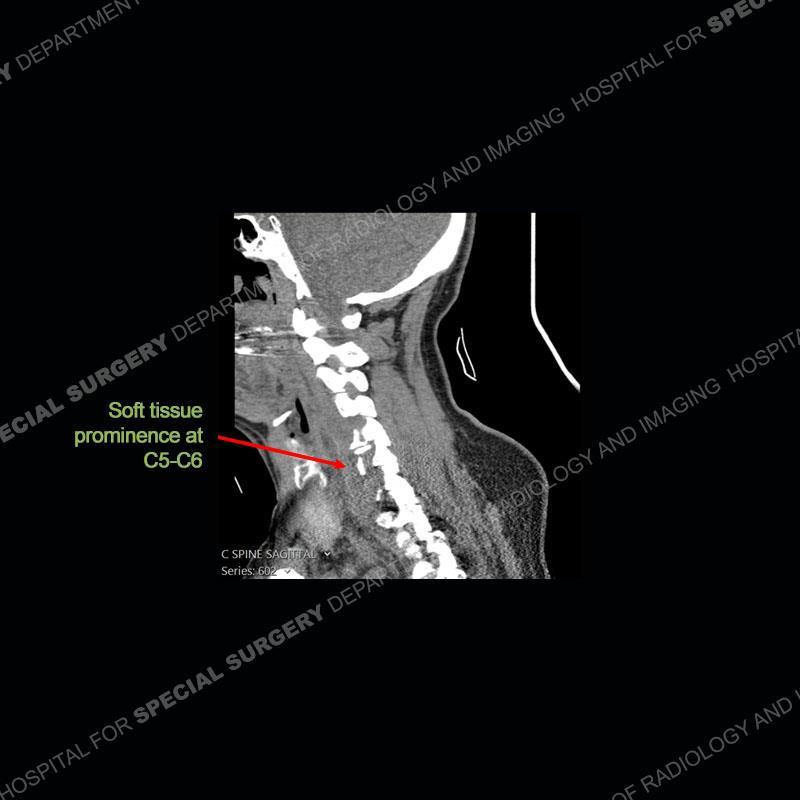

The radiographs demonstrate a prevertebral soft tissue fullness centered at C5-C6 that persists even on extension. There is a slight loss of disc height at C5-C6. The CT more readily shows the prevertebral soft tissue swelling at C5C6 where there is a punctate focus of gas. On the MRI, there is a marked amount of edema and a heterogeneous collection in the prevertebral soft tissue at C5-C6. Edema is present of the C5 and C6 vertebral bodies with a loss of the normal architecture about the disc space. A heterogeneous epidural collection has formed that causes compression of the spinal cord asymmetric to the left side and also precipitates severe left sided neural foraminal stenosis.